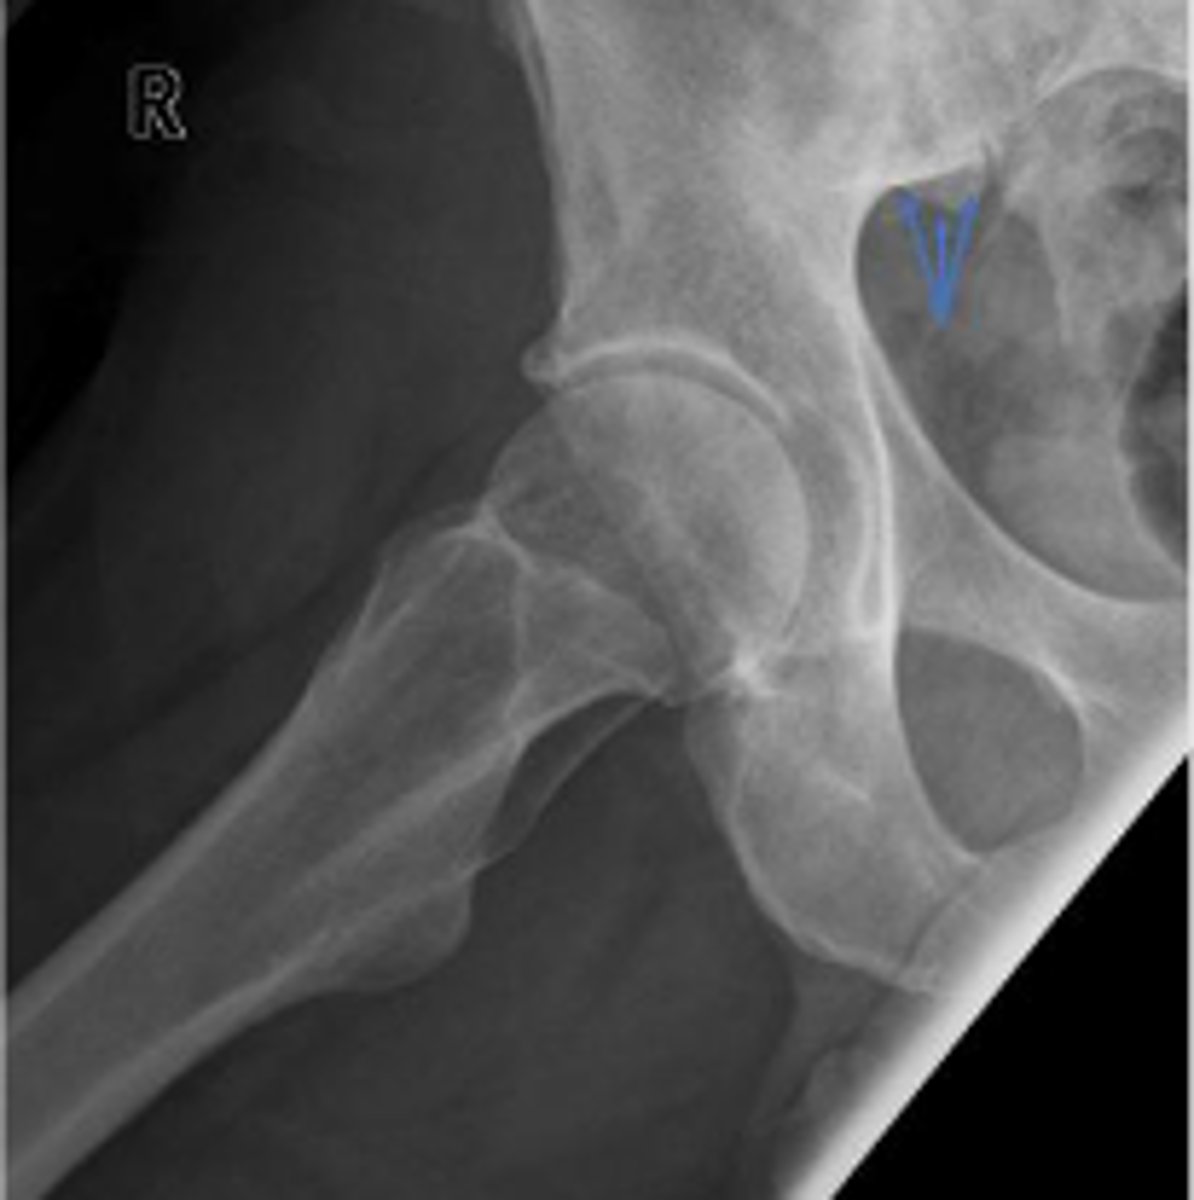

Bilateral frog leg view

What is the name of the radiographic view?

Phleboliths

What are the arrows pointing to?

Left and right posterior inferior iliac spine

Right posterior inferior iliac spine